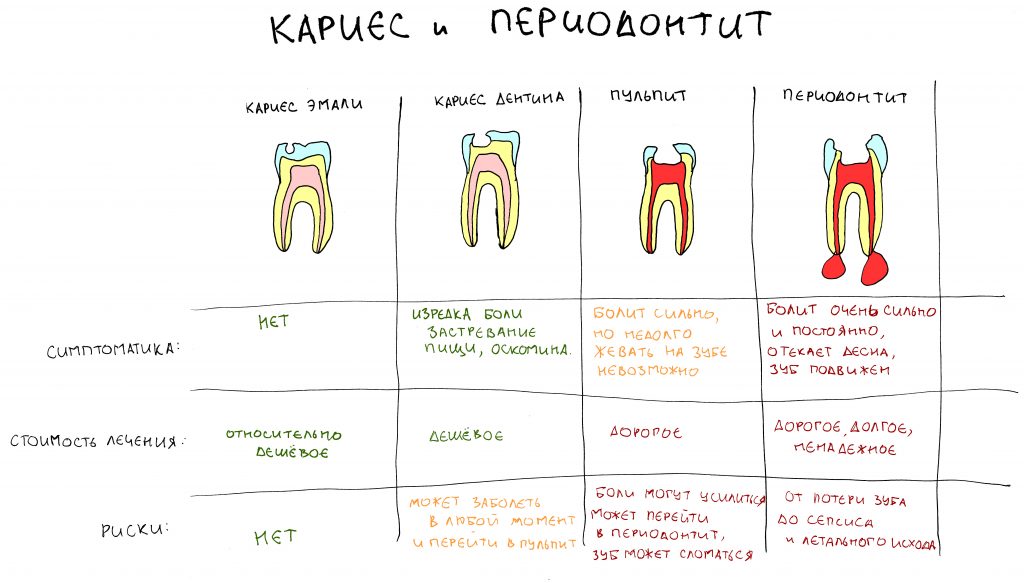

Если не брать какие-то несчастные случаи в виде вывихов и переломов, то в 99% причиной удаления зубов являются осложнения кариеса и заболеваний пародонта. Будем честными в том, что причина осложнений — пофигизм и отсутствие своевременного и правильного лечения.

Сколько раз, будучи в аптеке, я слышал: «Есть у вас что-нибудь от зубной боли или воспаления десны?». Люди пачками жрали анальгин пачками, изводили литры «Метрогил-дента», но до последнего откладывали обращение к стоматологу. Поэтому хирург-стоматолог был самым востребованным доктором в стоматологической поликлинике. Не могу не отметить, что в последнее время ситуация меняется — наконец, все поняли, что лечить кариес дешевле, чем пульпит, и что поддержание здоровья зубов — это не только стильно, модно, молодежно, но еще и выгодно.

Так вот, если пофигизм в отношении собственных зубов приводит к их утрате, то почему с имплантатами должно быть иначе? Ну да, они ж не болят! Они ж неживые!

«Чо им будет?» — говорит пациент, но потом искренне удивляется, когда мы планируем лечить периимплантит в области установленных 4-5 лет назад имплантатов.

Да, имплантат вместе с супраструктурой — неживая биоинертная металлическо-керамическая конструкция. Но имплантат находится в живых тканях, и эти ткани чувствительны к микрофлоре полости рта и травматическому воздействию. Они могут воспаляться и болеть. В конце концов, периимплантит — это же не повреждение самого имплантата, это воспаление окружающих имплантат тканей.

Так вот, если в случае с зубами появление кариозной полости и боль заставляют тебя срочно обратиться к стоматологу, то имплантаты с установленными керамическими коронками, никак не болят и не разрушаются.

Из-за этого ты вряд ли сможешь прочувствовать проблему с ними раньше, чем на стадии катастрофы, когда развившийся периимплантит осложняет жизнь, а нам, стоматологам, остается только развести руками, а далее планировать удаление имплантата, последующую остеопластику и реимплантацию.

Периимплантит сам по себе не является показанием к удалению имплантатов. Он лечится, причем весьма успешно — но ровно до того момента, пока его лечения целесообразно с точки зрения медицины и финансов. Вместе с тем, перимплантит является причиной утраты интегрированных имплантатов в 99% случаев — когда пациент своим бездействием доводит клиническую ситуацию до катастрофы.

Чем раньше обнаружена проблема — тем меньше усилий потребуется для её устранения и тем лучше будет результат. И наоборот.

Больше зубного налета — больше воспаление десны, больше деструкция кости и вновь — еще больше места для зубного налета. Всё это усугубляется отсутствием регулярности и навыков индивидуальной гигиены полости рта, в таких условиях утрата имплантатов является лишь вопросом времени. В принципе, с ними происходит то же самое, что и с естественными зубами, когда отсутствие индивидуального ухода и гигиены полости рта приводят к развитию кариеса и его осложнений, заболеванию десён и пародонтиту, а в итоге — у потере зубов.

Пожалуйста, напомни — каков срок службы твоих собственных зубов? Вроде как, они выданы тебе на всю жизнь? Но если ты теряешь свои собственные зубы из-за отсутствия внятного ухода и своевременного лечения — кто в этом виноват? И почему с имплантатами должно быть иначе?